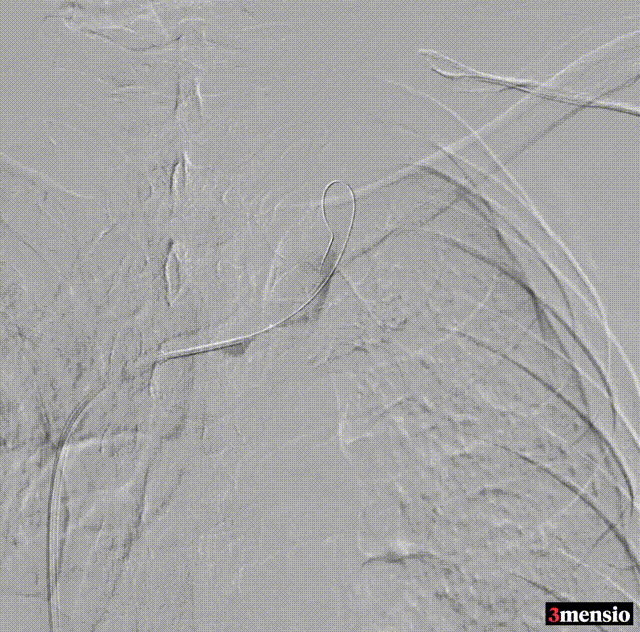

术前造影

建立通道

球囊扩张、支架置入